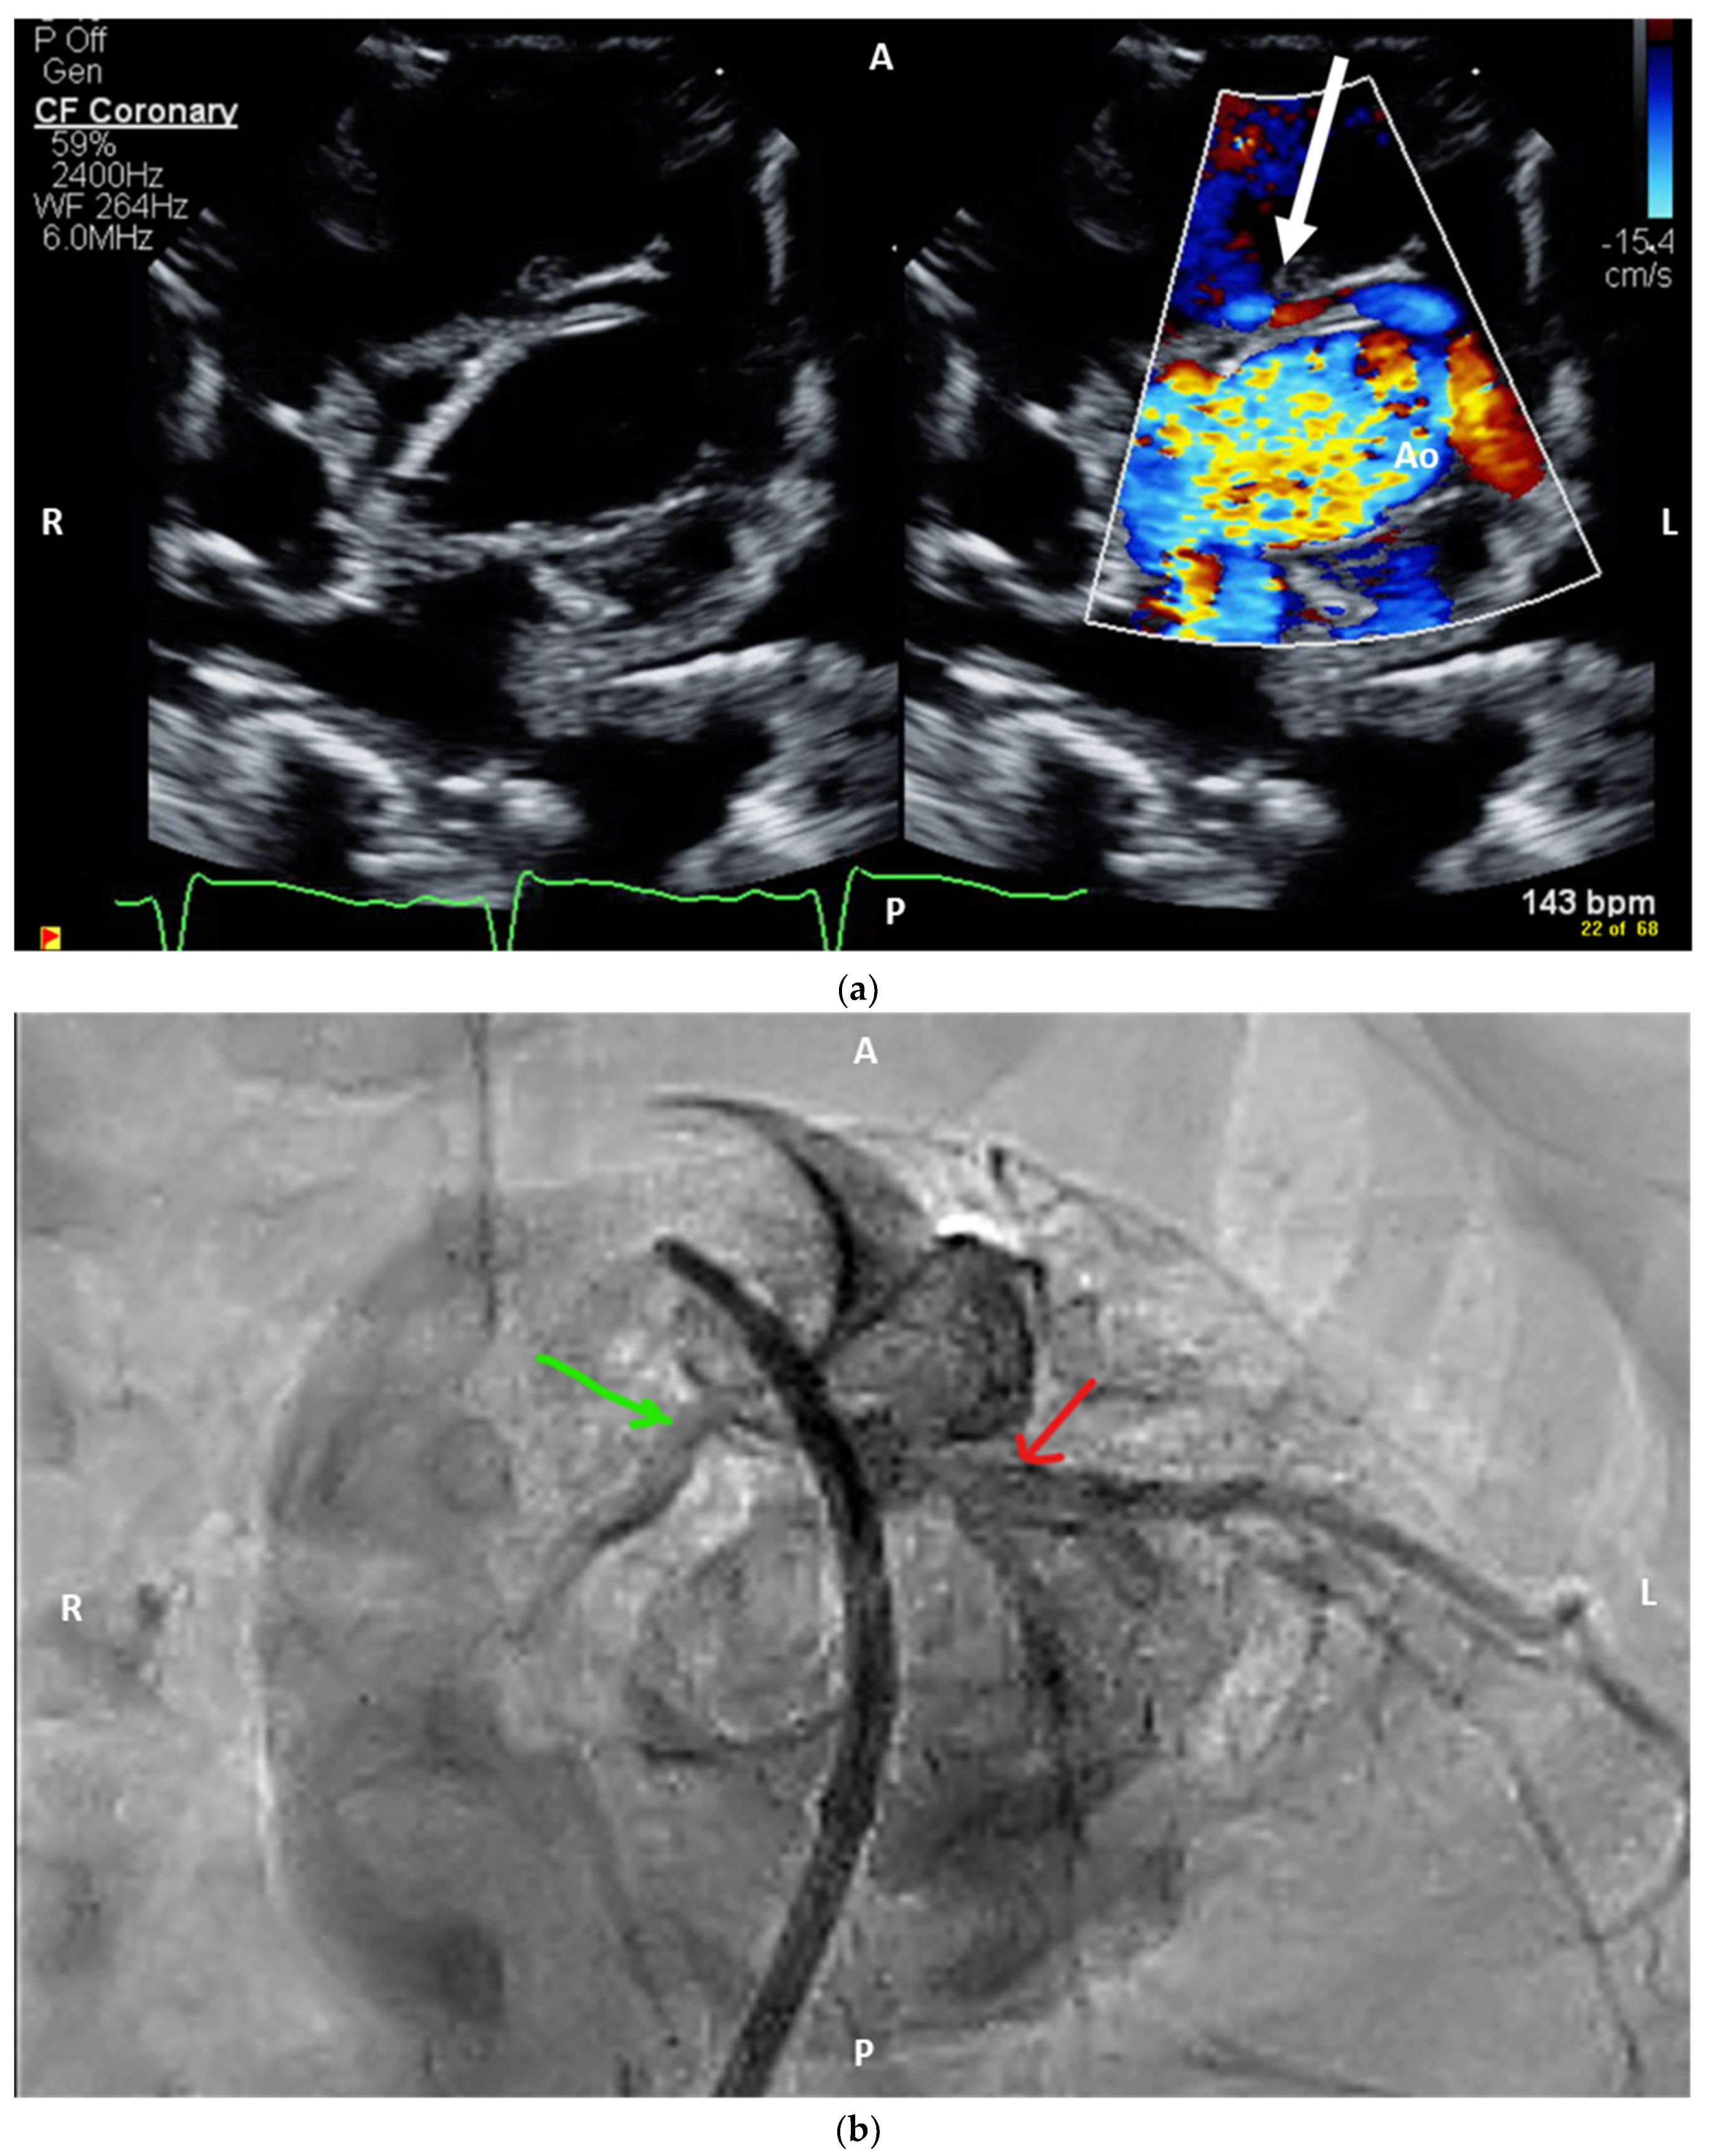

Figure 3. Salient postnatal imaging findings for Patient B. Focused imaging in Patient B demonstrated both coronary systems originating from the right-facing sinus (2LCx*, R) and intramural course of the left main coronary. (a) Trans-thoracic echocardiography for Patient B demonstrating the orifice of the left coronary artery that is eccentric and in close proximity to the intercoronary commissure. The proximal segment of the left coronary artery (white arrow) is inter-arterial, with suspicion of an intramural course. (b) Conventional angiography (RAO 13 degrees, caudal 43 degrees) demonstrating the right and left coronary arteries originating from the rightward-facing sinus (green arrow) and the left coronary coursing behind the aorta prior to its bifurcation (red arrow). Ao = aorta, A = anterior, P = posterior, R = right, L = left.